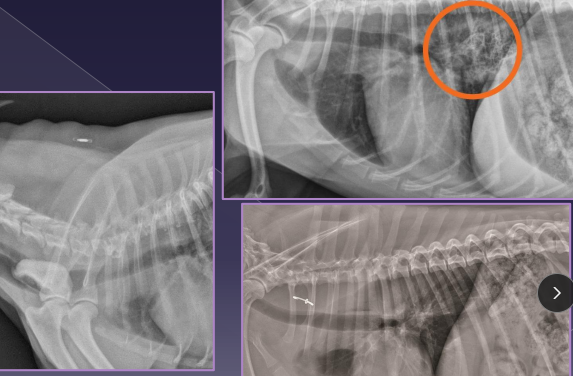

Vascular Ring Anomalies

Et: Persistent Right 4th Aortic Arch (PRAA), constriction at esophagus

Sig: young, GSD, Irish Setter, Boston, Siamese, Persian

Cs: solid food regurge, aspiration pneumonia(2ndary), failure to thrive, poor weight gain

Dt: contrast esophagram (enlarged @ base), CT/angiogram

Check for cranial megaesophagus

Tx: Sx at 10-12w (lig arteriosum division)

Fair to good prognosis

the fibrous remnant of the fetal ductus arteriosus